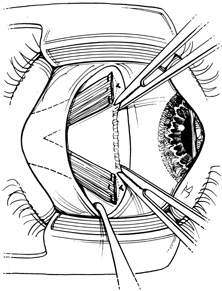

Step 2. A Stevens hook is brought from beneath the muscle to perforate it at its midpoint. Then, the hook is used to split the muscle into equal halves for a distance of 15 mm posterior to its insertion (Fig. 2). Blunt Westcott scissors may be used to complete the ends of the split, particularly at the muscle insertion (Fig. 3).

Fig. 2. A Stevens hook is brought from beneath the muscle to perforate it at its midpoint. Then, the hook is used to split the muscle into equal halves for a distance of 15 mm posterior to its insertion.

Fig. 3. Blunt Westcott scissors may be used to complete the ends of the split, particularly at the muscle insertion.

Step 3. Two double-armed 6-0 Vicryl sutures are used to secure each half of the muscle separately (Fig. 4). Both halves of the muscle are disinserted from the sclera (Fig. 5).

Fig. 4. Two double-armed 6-0 Vicryl sutures are used to secure each half of the muscle separately.

Fig. 5. Both halves of the muscle are disinserted from the sclera.